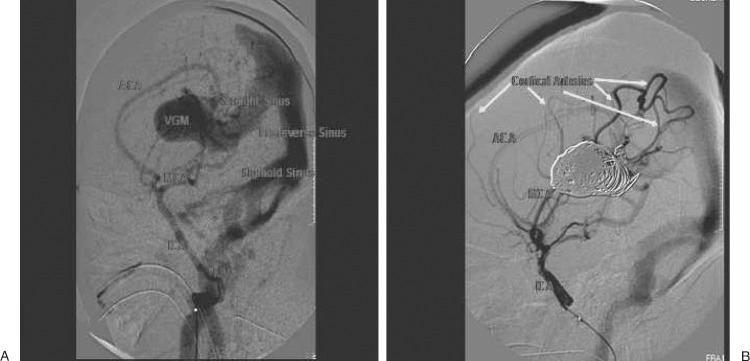

Vein of Galen aneurysmal malformation presenting as severe heart failure in a neonate.

Outcome of Neonates with Vein of Galen Malformation Presenting with Severe Heart Failure: A Case Series.

Epidemiology, Diagnostics, and Management of Vein of Galen Malformation.

Vein of Galen malformations: review.

Vein of Galen malformation: diagnosis and management.

Vein of Galen aneurysmal malformations. Report of 36 cases managed between 1982 and 1988.